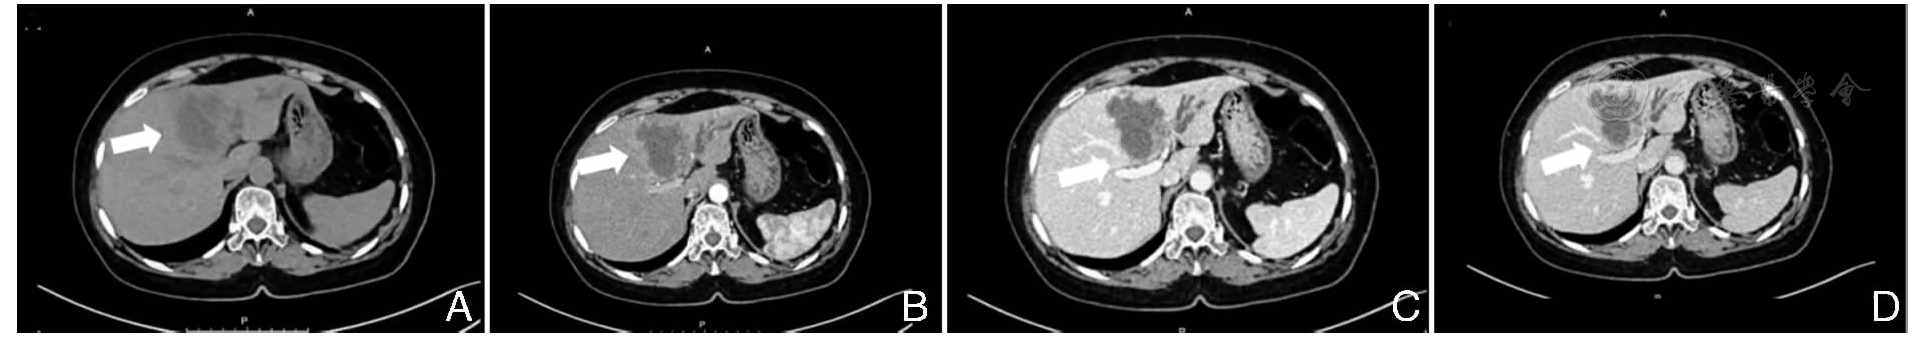

A patient admitted to the Hepatobiliary Surgery Department of Wuxi Xishan People′s Hospital in Mar. 2025 with cholecystolithiasis and acute cholecystitis was subsequently found to have a left hepatic lobe mass adjacent to the portal fissure (sagittal part). Clinical diagnosis confirmed ICC, cholecystolithiasis, and acute cholecystitis. After systematic evaluations including cardiopulmonary function, hepatic functional reserve, and tumor staging, a laparoscopic surgical strategy was formulated.